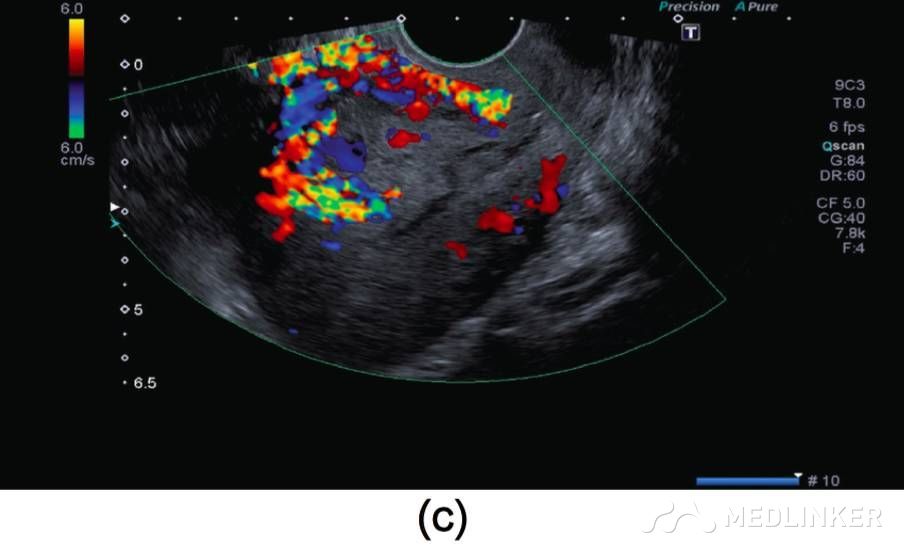

患者35岁,G2P1A1,2周前因稽留流产(9周),于外院行刮宫术(图1a)。该患在首次刮宫术后因怀疑宫腔内血肿,在术后观察的一周内反复性刮宫。最终因为患者阴道流血及转入我院后,终止刮宫。入院后查:Hb:11.2g/dL,Htc:35.1%,hCG:3518mIU/mL。阴式超声示子宫前壁可见60×60×56mm(103cm3)大小杂乱回声区(图1b)

图1 (a)刮宫术前彩超示: 宫内死胎, 妊娠9周, 未见子宫动静脉瘘;(b)子宫前壁可见大小60×60×56mm(103cm3)杂乱回声区, 并延伸至子 宫左侧 ;(c)彩色多普勒超声检查示极丰富“五彩镶嵌”彩色血流